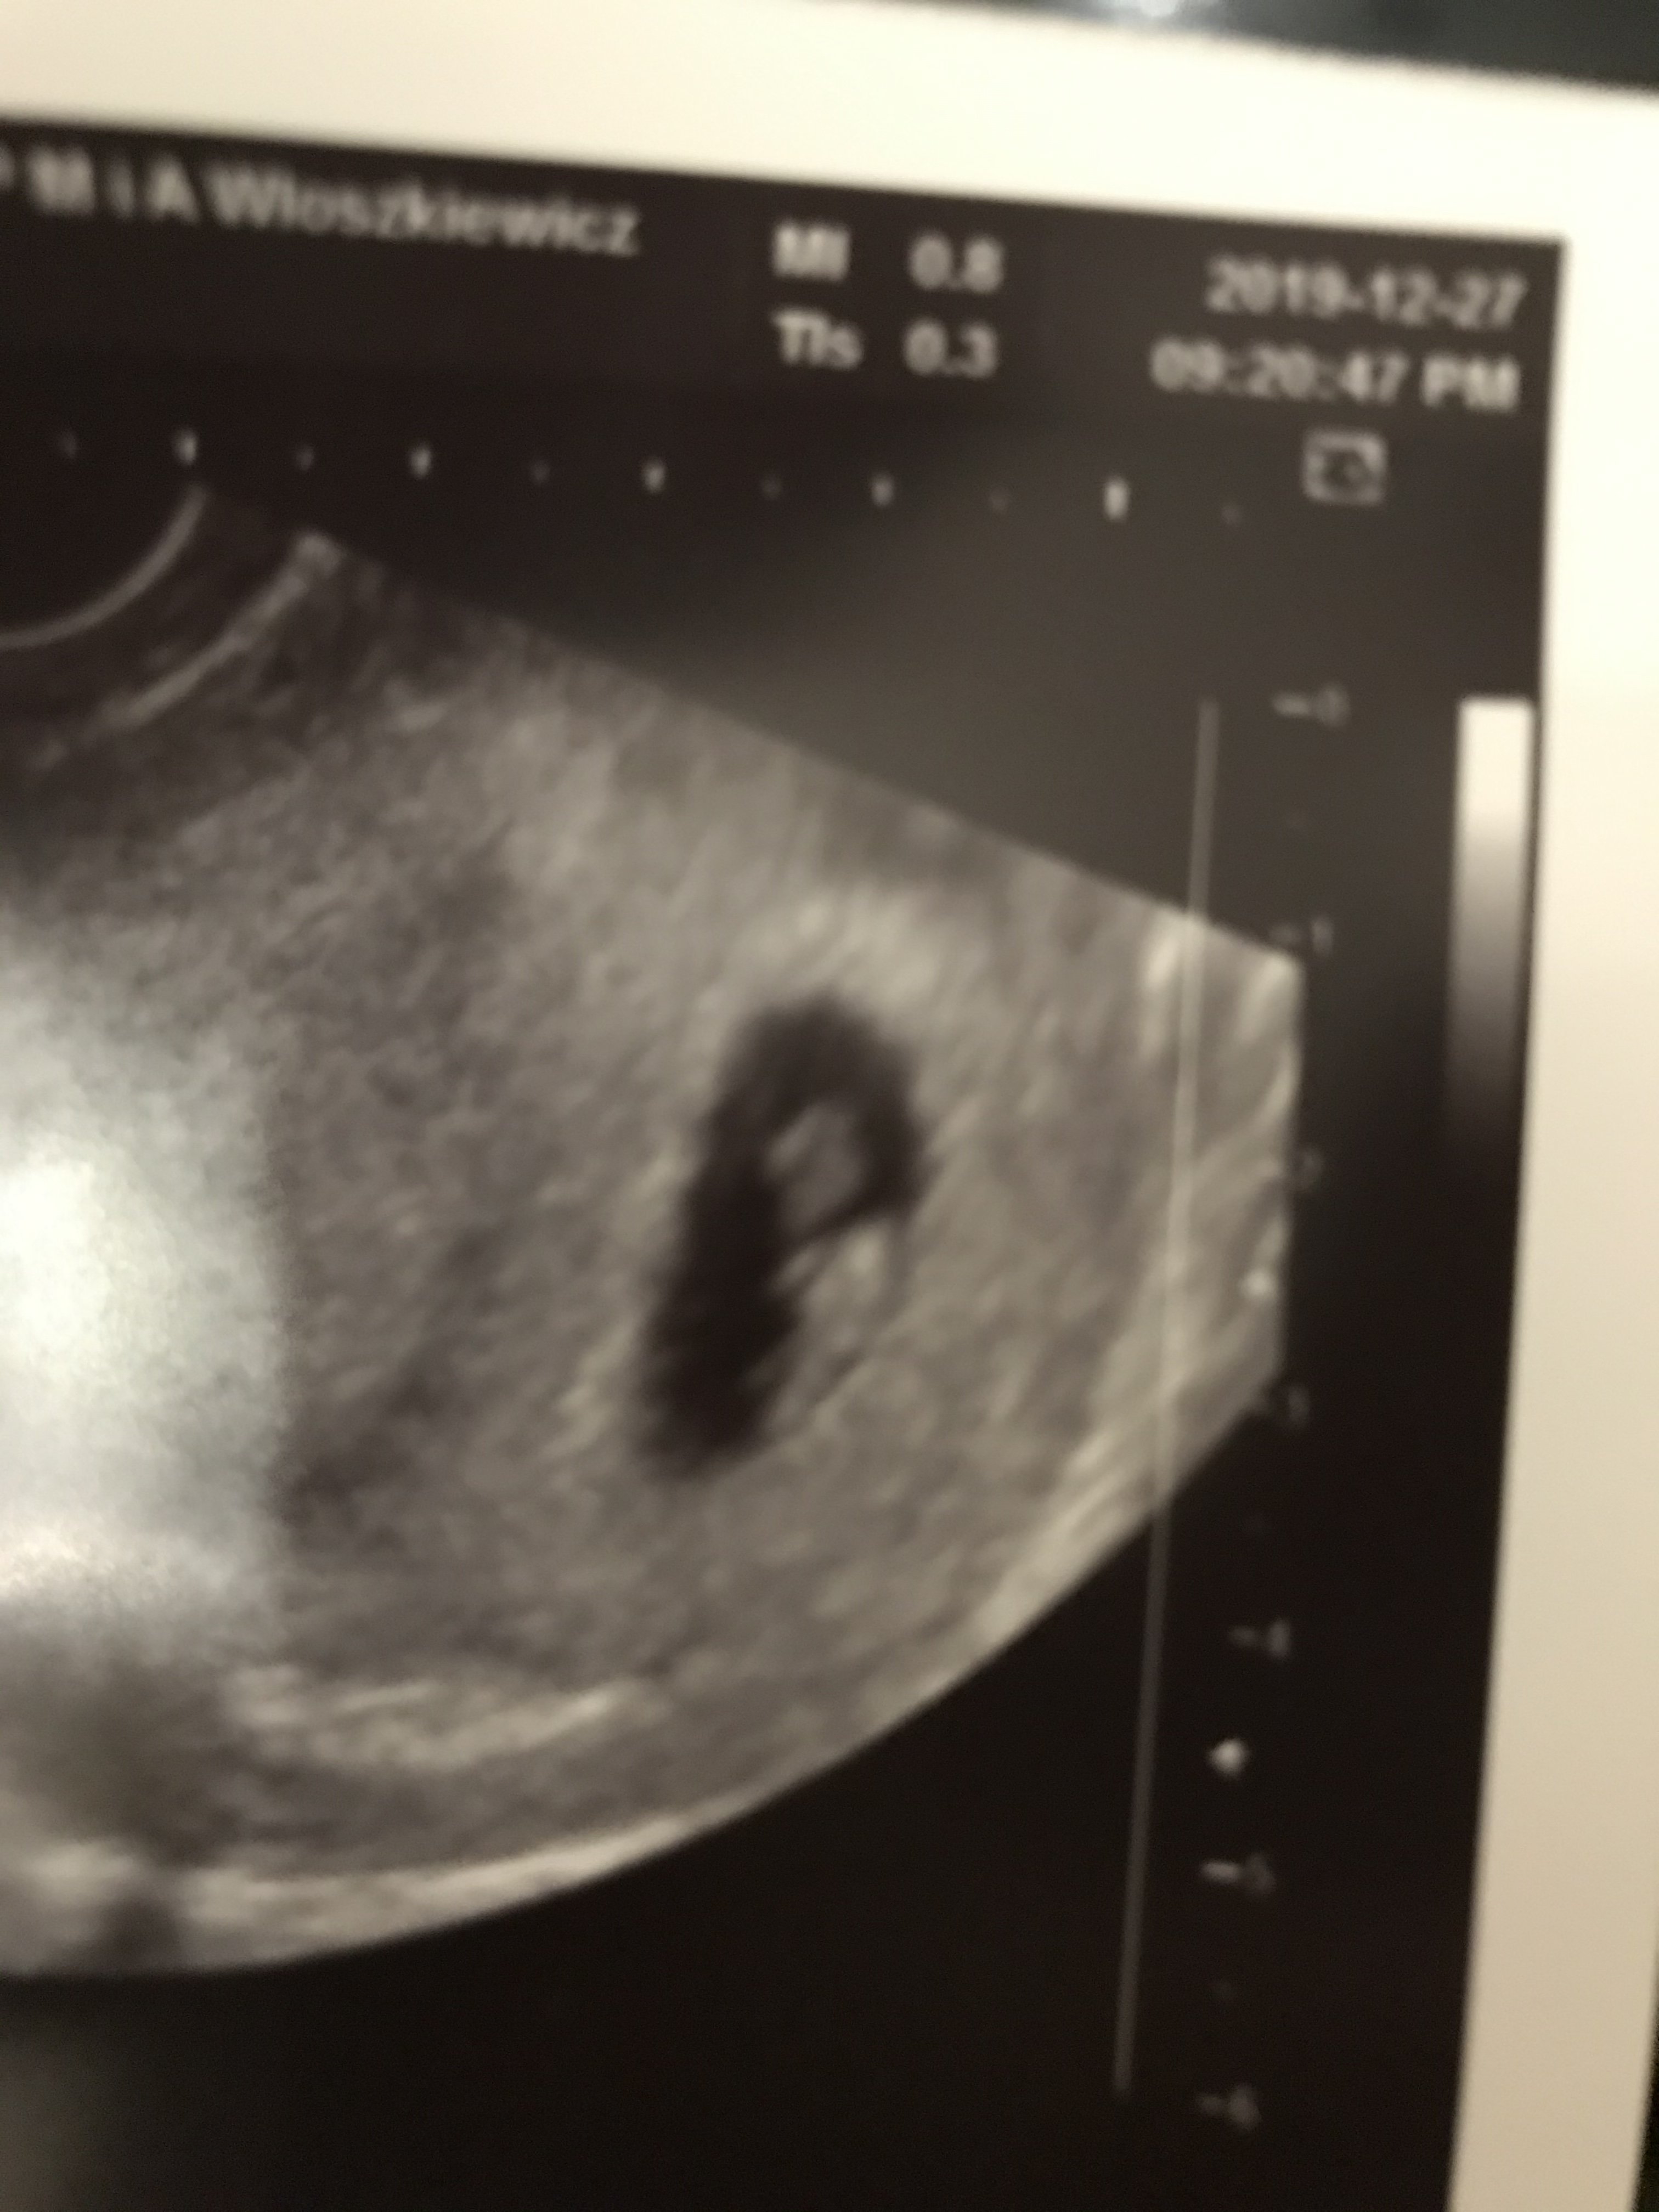

Dziewczyny oszalalam i dzwonilam do ginki czu nie znajdzie sie miejsce dla wariatki na szybciutkie usg (bo wizyte mam za tydzien ale chodze zdenerwowana) 😂 no i sie znalazlo. 7+0 wg usg wiec dzien wiecej niz z om. Serduszko przepieknie bije i jestem spokojniejsza. Ta kuleczka wyzej to cialko zolte a nizej maluszek.

Załączniki

• 672F46FA-619F-45BA-BB95-B531F463C660.jpeg

672F46FA-619F-45BA-BB95-B531F463C660.jpeg

798,3 KB · Wyświetleń: 118